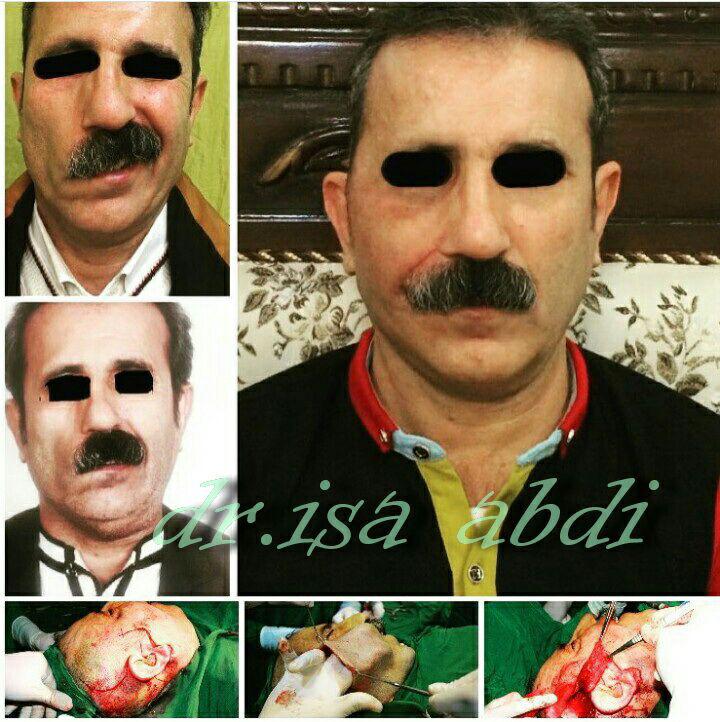

درمان مشکلات بافت نرم و شکستگیهای فک و صورت

جراحی تومورها، کیستها و بیماریهای خوشخیم و بدخیم در فک و صورت

جراحی آسیبهای تروما در فک و صورت ناشی از تصادف، جنگ، تومور و…

جراحیهای مفصلی در ناحیه فک و صورت

جراحی ترمیمی و زیبایی فک و صورت و جمجمه و گردن